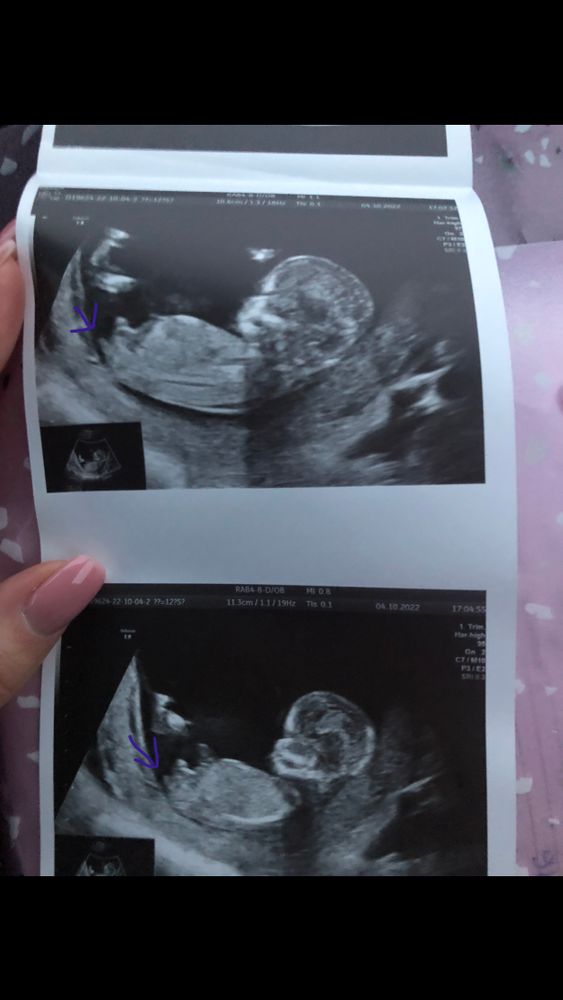

Узи на 13 неделе

Пол малышаБыла на узи ,врач показала 3 бугорка 😄

не могу определить по фото где именно половые бугоки,а где ноги или что-то другое 😅на нижнем фото -как будто вообще 3 штуки )

может кому будет более понятно -хотелось бы услышать предположения )

Вера

Я тоже не могу понять где именно тот бугорок))) но они все кверху,а значит- там скорей всего мальчик)

А я виду,что ребятенок закинул ножку на ножку, вот так) так что сказать что-нибудь сложно.

Enot v teme , вот и мне кажется что это ноги ,особенно судя по 3д фотке -там обе ноги вверх

тогда то что ниже ноги -это вроде на девочку похоже ☺️(Это я уже сама себя убеждаю ,похоже 😅))

Kseni, может быть часть ноги. Но то что я указала это точно половой бугорок. У сына такой же был